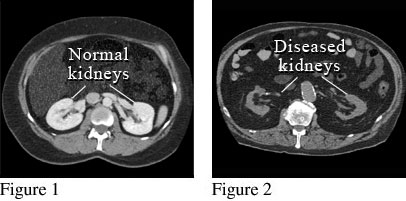

Figure 1 shows a picture of a computed tomography (CT) scan of two normal kidneys, looking from the top of the head down. A special dye (contrast material) was used for this scan. Figure 2 shows a picture from a different CT scan of two kidneys that are abnormal. These kidneys are small and misshapen from scarring due to disease.